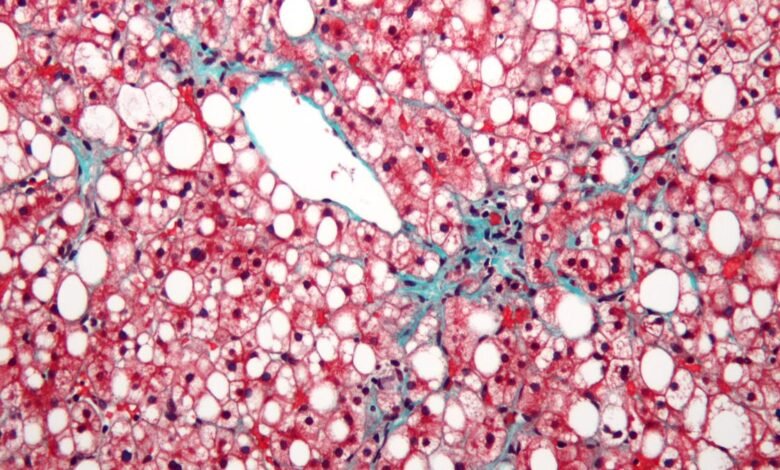

O fígado gordo significa literalmente obter excesso de gordura no fígado. Com o acúmulo dessas gorduras, o fígado começa a inchar e, com o tempo, perde sua capacidade de funcionar corretamente, o que leva a vários problemas de saúde. A principal razão é a incompatibilidade entre as calorias que consumimos e as calorias que queimamos. Quando comemos mais alimentos gordurosos e densos de calorias-como alimentos processados, carne vermelha, coisas fritas e alimentos ricos em petróleo-e não queima calorias adequadas através da atividade física, o excesso de calorias é convertido em gordura e isso começa em acumulação no fígado.

Inicialmente, os lipídios no fígado podem ser pequenos e inofensivos, mas se os hábitos prejudiciais persistirem, esses depósitos se acumulam gradualmente em níveis perigosos, levando a doenças hepáticas gordurosas. Os principais acionistas, neste caso, são uma dieta prejudicial, um estilo de vida estável e o consumo de calorias são mais do que queimaduras corporais. Para evitar a doença hepática gordurosa e até o oposto, é necessária modificar um estilo de vida abrangente que se concentra na dieta e na atividade física.

O fígado sebáceo pode parecer prejudicial a princípio, mas se for ignorado, for ignorado, Pode ser aplicado Em complicações graves e pode ameaçar a vida. Sem intervenção oportuna, o fígado sebáceo pode avançar da hepatite, conhecida como hepatite, para o desenvolvimento de um tecido cicatricial chamado fibrose e, eventualmente, à fibrose hepática, o que causa danos permanentes e irreversíveis ao fígado. A fibrose hepática é uma fase grave da doença hepática, pois o órgão não pode mais desempenhar suas funções vitais de maneira eficaz. Quando a doença atinge estágios avançados, o único tratamento disponível pode ser o processo de transplante de fígado, que é um procedimento muito complexo e pioneiro.